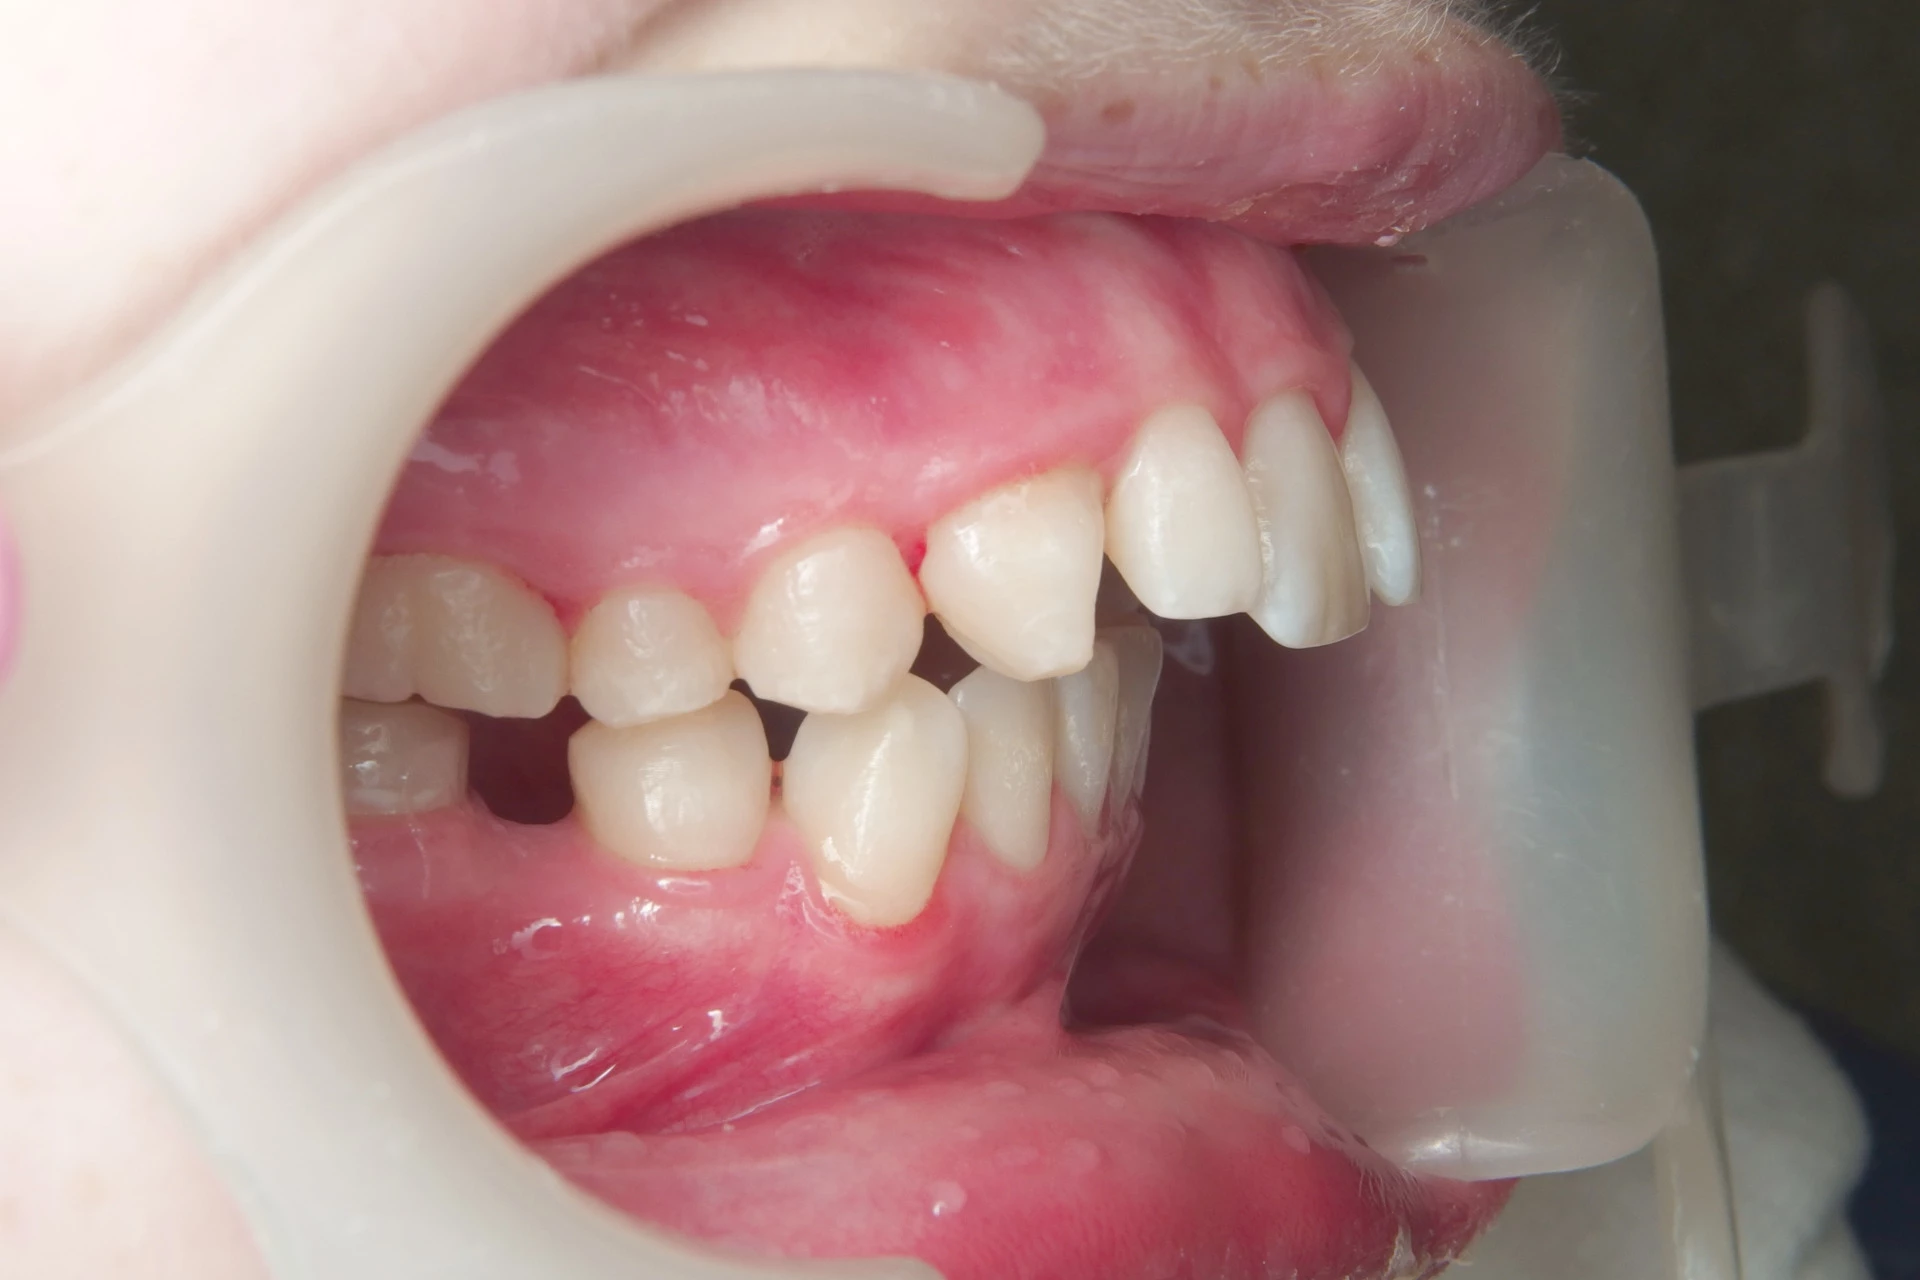

Vårt arbeid

Alle pasienter som vises har gitt skriftlig samtykke til at bildene kan brukes på klinikkens nettside.